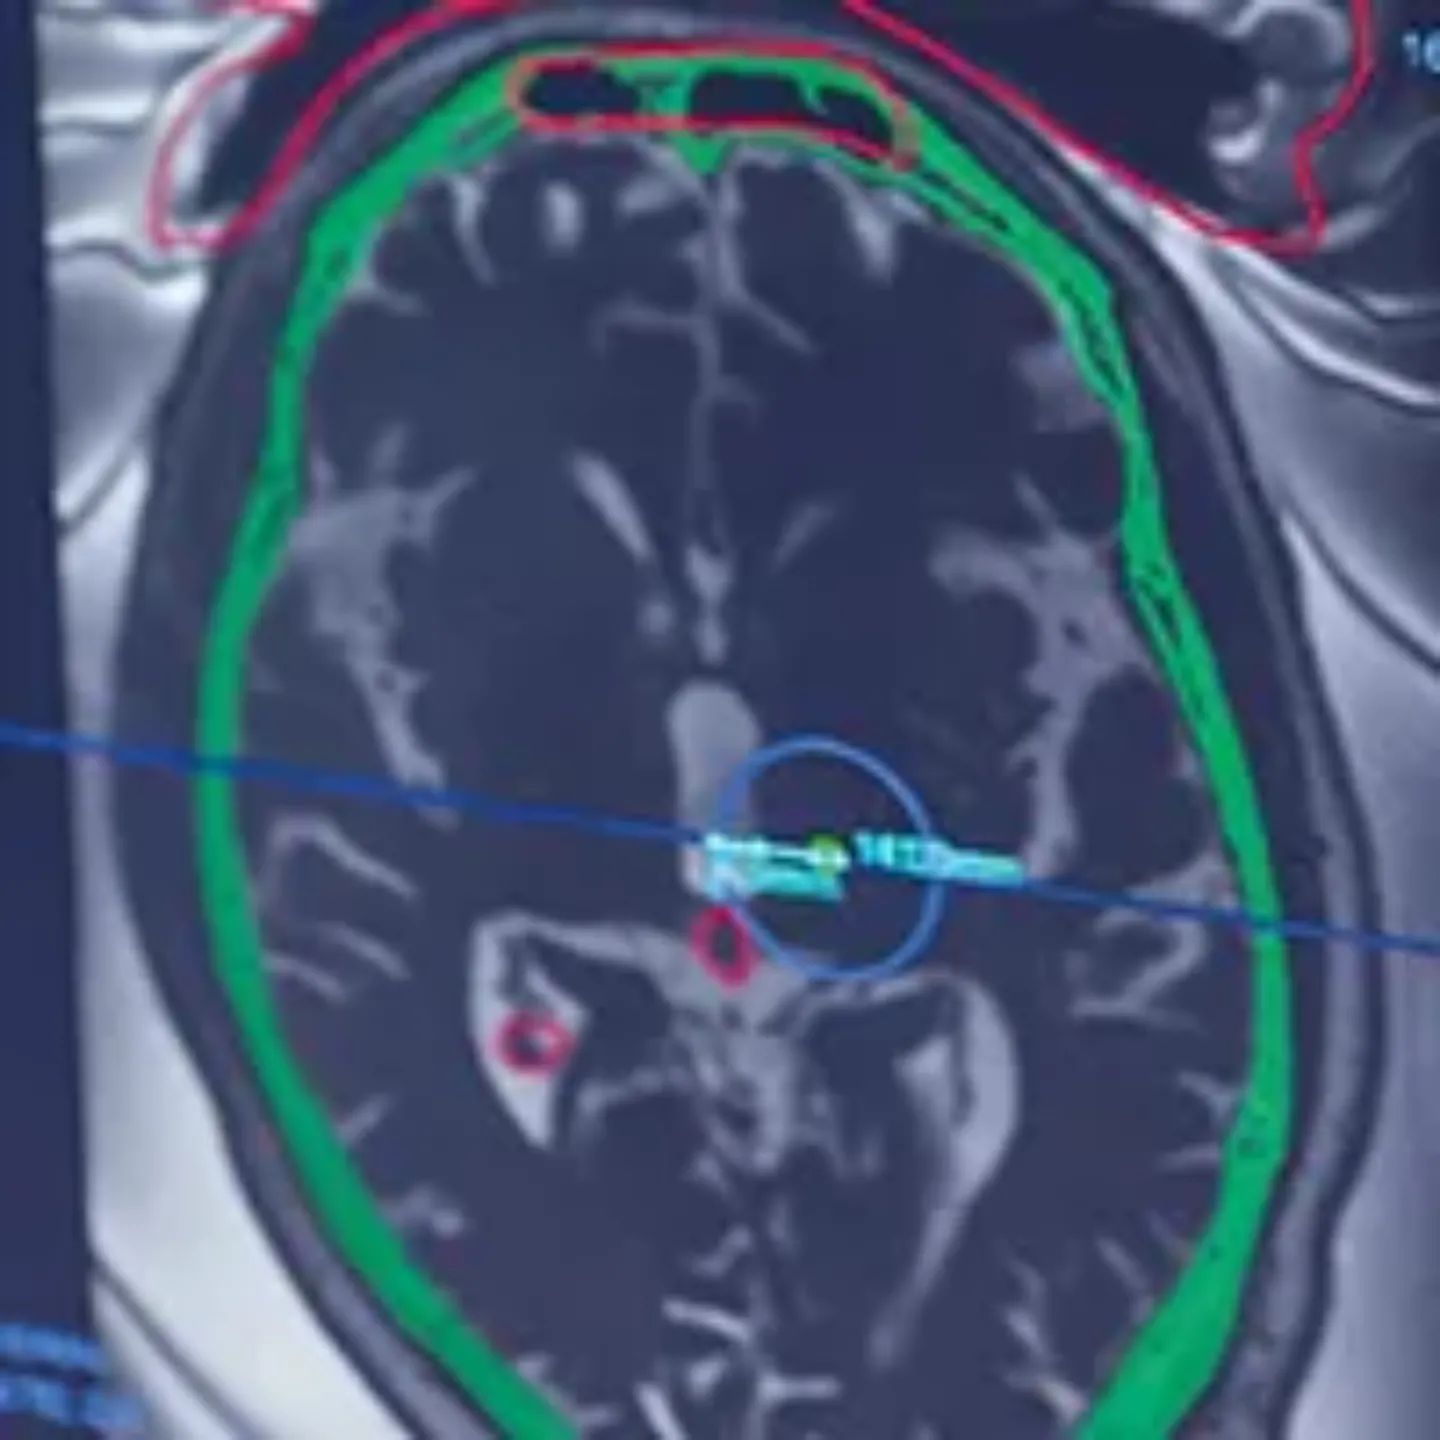

"Con el HIFU ganas de nuevo tu calidad de vida"